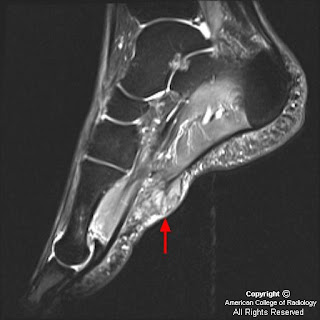

Плантарный фиброматоз (синдром Леддерхозе, описан им в 1897 г) в отличие от пальмарного фиброматоза редко сопровождается сгибательиой контрактурой. Поражает обычно медиальный отдел подошвы стопы (плантарный апоневроз) и имеет вид узелков, с течением времени достигающих 4—5 см в поперечнике. Узлы обычно плотные, множественные, связаны с фасциальными образованиями. Микроскопически новообразованная ткань богата фибробластоподобиыми клетками.

Подошвенный фиброматоз

Плантарный фиброматоз